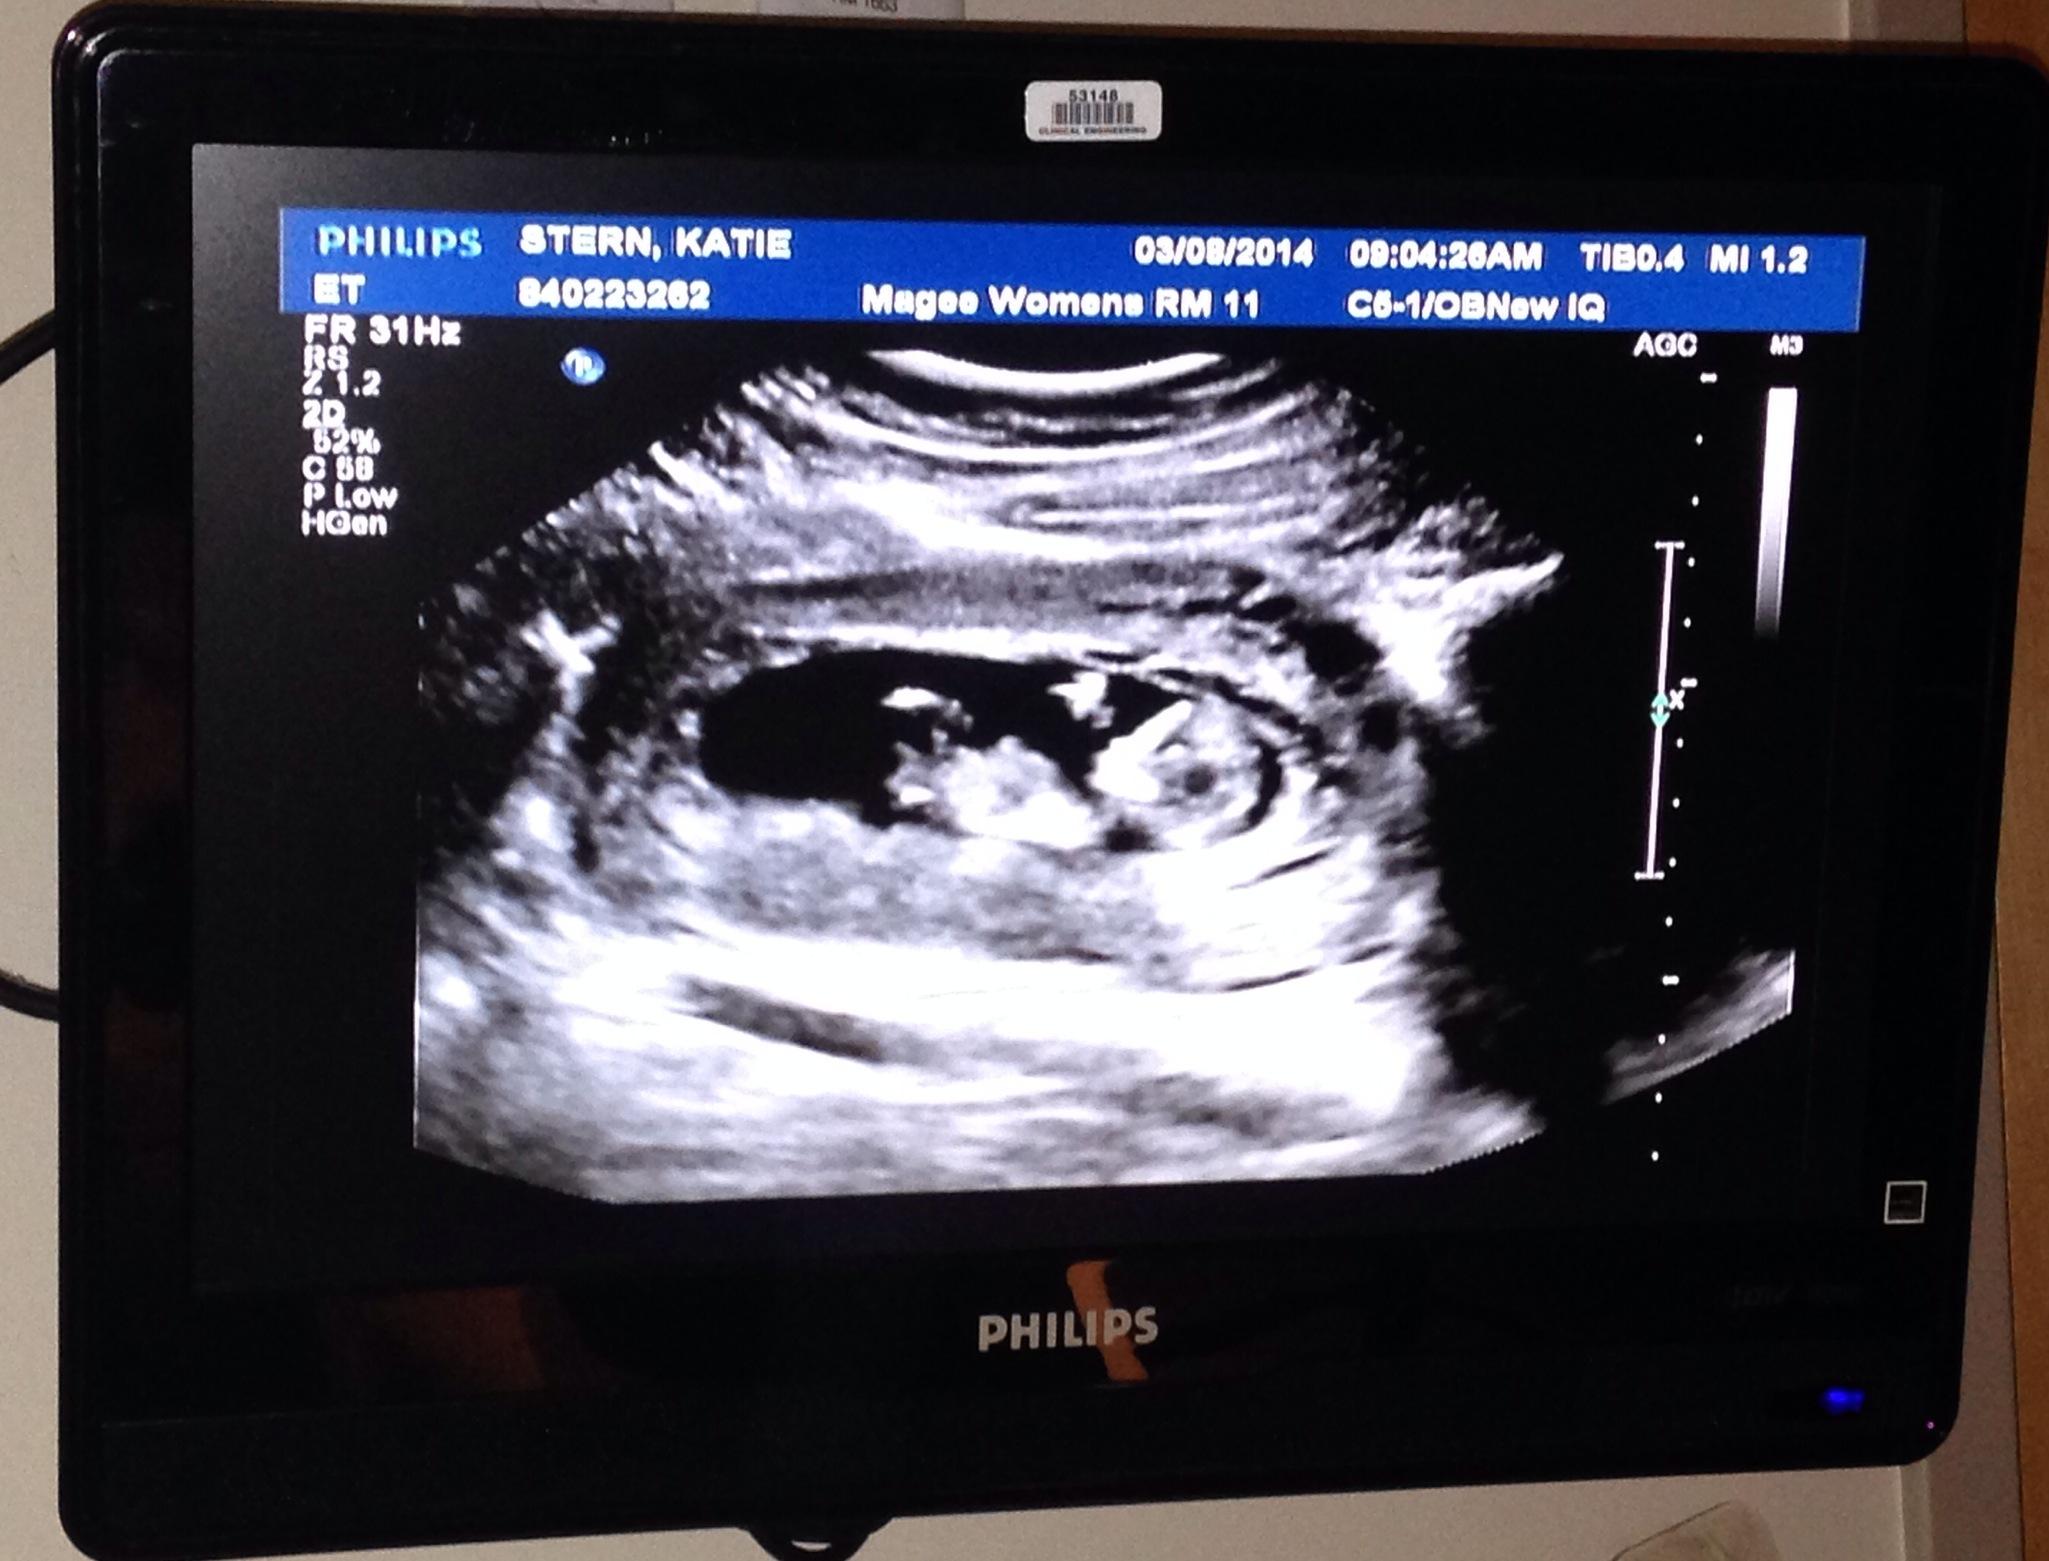

We were lucky enough to have our first ultrasound on February 3 and we got to see our little baby! What an amazing site – to see that little flicker on the screen of a healthy and strong beating heart. Everything looked great! Our official due date is September 16, 2014. We had another appointment earlier this month, March 14, and we got to “hear” the heartbeat. Let me tell you, you wait for the longest time and you have no idea the overwhelming emotion to hear the most amazing sound. It gives you so much hope in what is happening and your heart just grows tremendously to know your little baby is doing so well. We had an ultrasound the week before and both Dan and I were shocked at how much growth had occurred. To actually be able to see little hands and feet – he/she would not stay still the entire time, but the technician said that was a good thing that it was moving all around. Such distinction and such growth in what seems to be so little time – it’s just so exciting!

And from our second ultrasound/genetic screening (March 8).